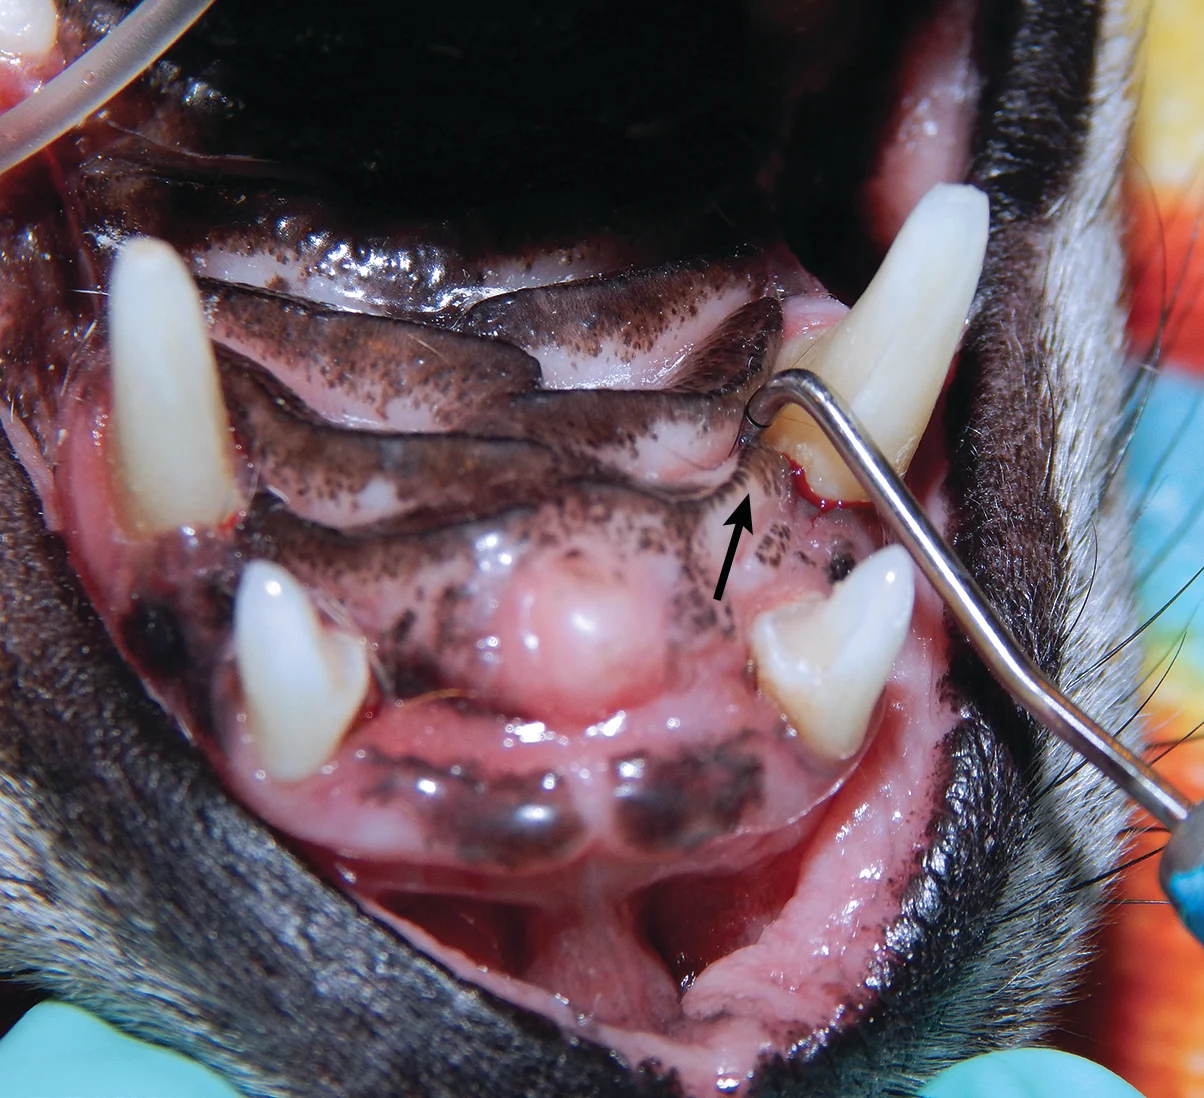

Oronasal fistulas may often be present prior to surgical extraction of maxillary teeth (Figures 6 and 7) but can also be a result of the surgical procedure. Although any maxillary tooth extraction can result in an oronasal fistula, it is most common following extraction of a maxillary canine tooth. Inadequate healing may lead to chronic oronasal fistulation (Figure 8). The quality of the tissue used to close the fistula and lack of wound tension are especially important in closure of oronasal fistulas. Development of a healthy recipient bed for the flap (Figure 9) and use of an Elizabethan collar to prevent self-trauma by the patient can also reduce flap failure.4

A dental probe used to demonstrate the presence of an oronasal fistula (arrow) affecting the right maxillary canine tooth

Appearance of the oronasal fistula in Figure 6 after surgical extraction of the right maxillary canine tooth. Purulent exudate (arrow) is visible in the nasal cavity through the oronasal fistula.